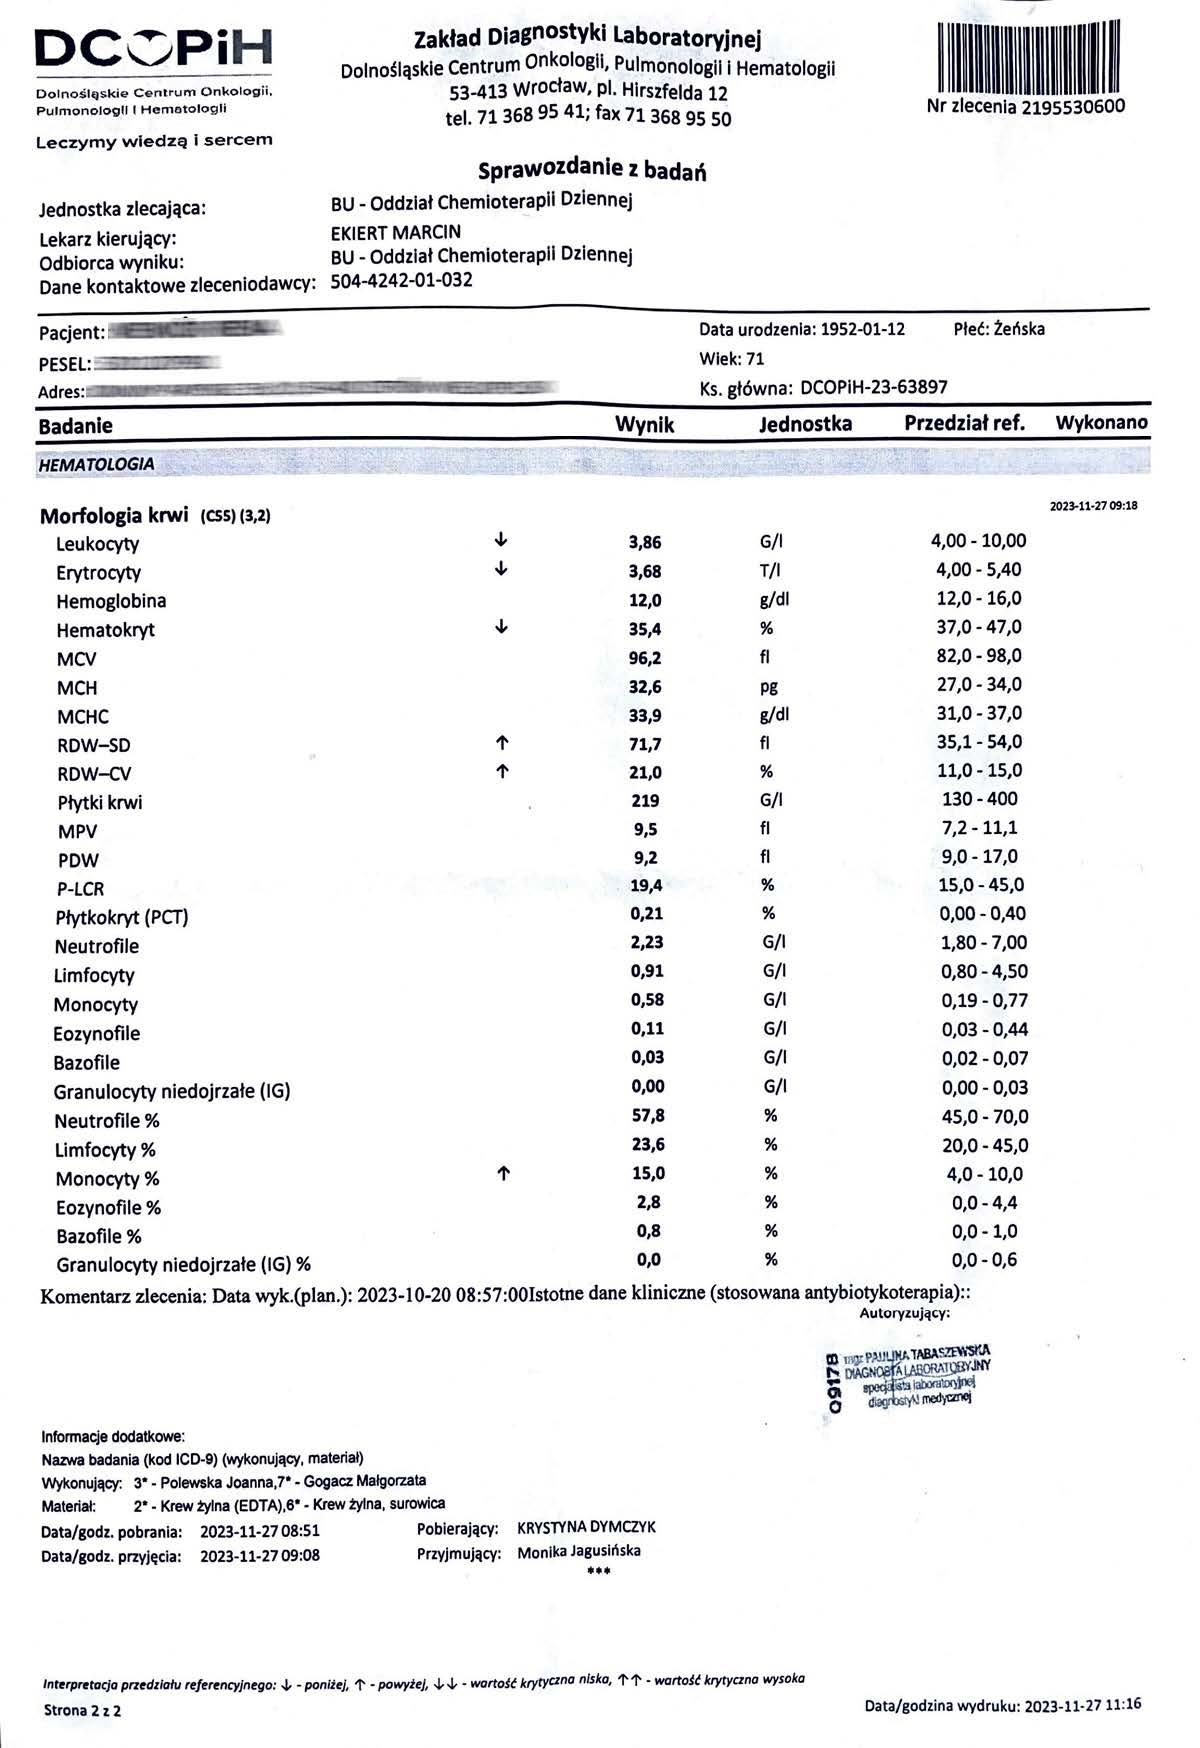

EFEKT PREPARATU NA RAKA PIERSI

Kobieta lat 71, rak piersi w IV stadium, zaawansowane stadium metastazy. W trakcie stosowania preparatu odnotowano spadek markerów Ca 15-3 z wartości 140,0 U/ml do 78,3 U/ml oraz spadek markeru CEA z 11,8 ng/ml do 8,4 ng/ml w zaledwie 3 miesiące, odnotowano stabilność szpiku. Wyniki wykazują zahamowanie progresji, dodatkowo odnotowano cechy uzupełniające terapię farmakologiczną, więc jest to jeden z przykładów wspomagania leczenia systemowego.